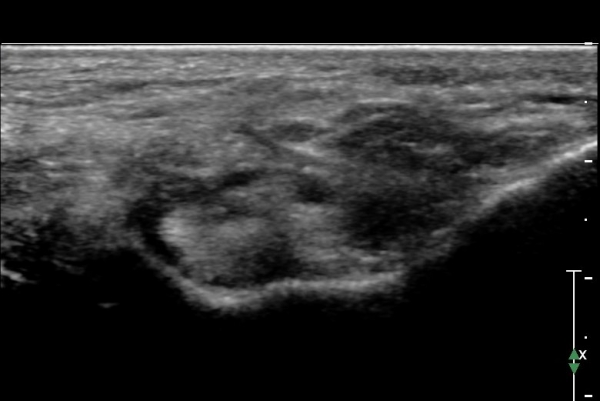

ÃÊÀ½ÆÄ ¼Ò°ß :  ¹ß¸ñ ³»Ãø Á¾´Ü¸é °Ë»ç¿¡¼­ Á¤»ó ÀûÀÎ ¼Ò°ßÀ» º¸ÀÓ(»çÁø 1).